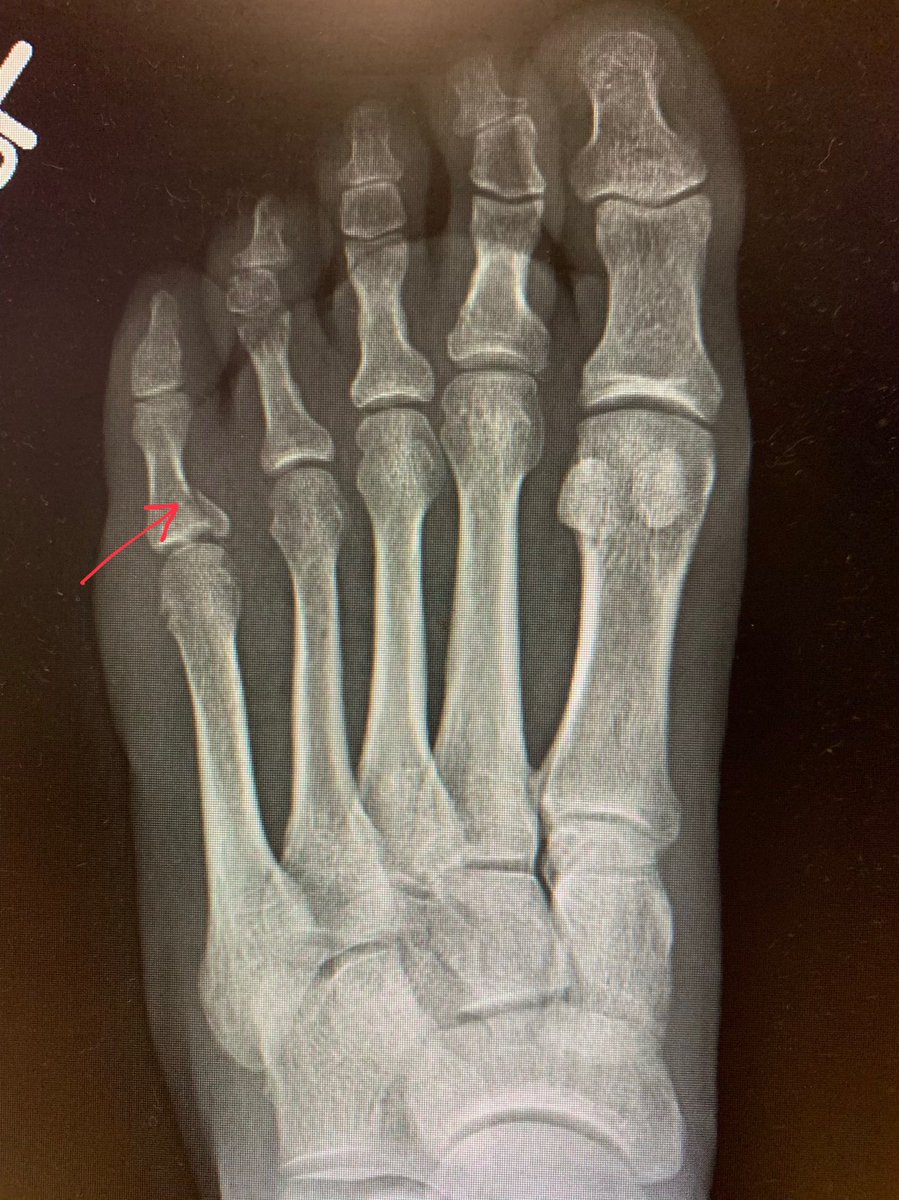

View Broken Pinky Toe Bone UK. A broken pinky toe will have more bruising and swelling than a sprained toe. The little toe (pinky) is the most common toe fractured.

Your big toe slants toward your other toes. It'll tell you it's broken far more frequently than it actually is. The pinky toe is the most commonly broken toe. A broken toe, also known as a toe fracture, is a very common injury, especially in athletes and those with active lifestyles.